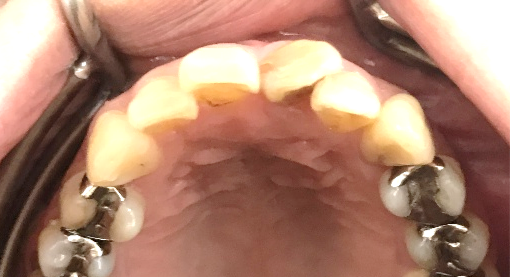

女性Mさん 40代(オールセラミック冠)

主訴

上の前歯をきれいにしたい。

治療内容

前歯4本を根管治療をし、オールセラミック冠を被せました。

所感

右の1本は、被せ物をしていましたが、すり減り形が変わり、変色もしていました。他の3本はすでに神経がない状態で、詰め物をしていましたが、詰め物及び歯自体も変色し、詰め物と自分の歯の境目のところからむし歯になっていました。治療後「きれいになって嬉しいです。治療して本当に良かったです。」と、とても喜んでくださいました。

オールセラミック冠4本:¥104,500×4本=¥418,000(税込)

Before

After